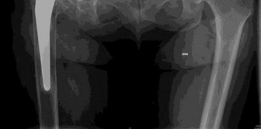

Given the complexity of the acetabular defect and the planned revision, advanced imaging was mandated to precisely quantify the volumetric bone loss and evaluate the integrity of the anterior and posterior columns. A multi-detector Computed Tomography scan of the pelvis with metal artifact reduction sequence protocols was obtained.

The coronal CT reconstructions provided a definitive assessment of the medial wall defect and the extent of superior migration. The imaging confirmed a severe cavitary defect extending into the ilium, with a focal segmental defect of the superior rim. The medial wall was critically thin, with focal areas of complete absence, allowing the medial aspect of the cup to protrude into the true pelvis. Importantly, the CT scan confirmed that despite the severe osteolysis, the anterior and posterior columns remained in continuity, ruling out a complete pelvic discontinuity.

Three-dimensional surface-rendered CT reconstructions were utilized for preoperative templating and spatial orientation of the defect. These 3D models are invaluable for visualizing the exact geometry of the remaining host bone and for determining the appropriate size and shape of structural allografts or highly porous metal augments required to restore the anatomic center of rotation.